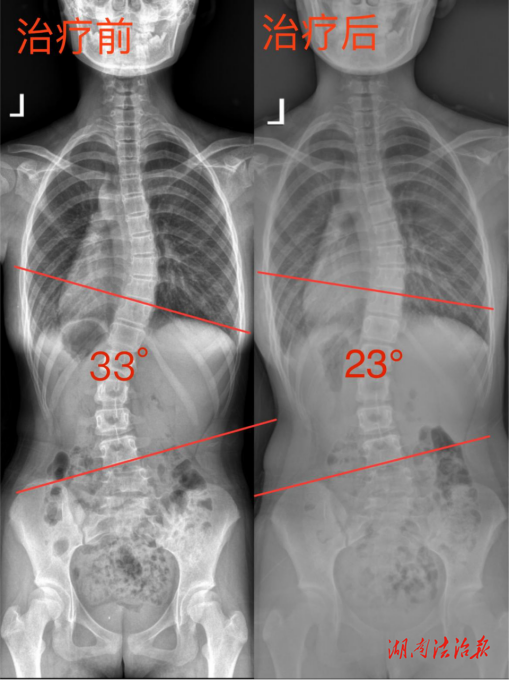

令人印象深刻的是,一位 12 岁的女孩,她在入学体检时被发现脊柱存在轻度侧弯。起初,家长并未带她到正规医院接受专业治疗,而是选择了一家声称能快速矫正的正骨馆,进行了为期一个月的正骨治疗。然而,女孩的侧弯不仅没有减轻,通过复查发现侧弯角度竟有所增加,家长心急如焚。来到夏令营后,多学科团队为孩子进行了详细的专业评估,依据她的具体情况制定了专属的干预方案。方案中既融入了中医药特色的推拿、体质辨识,用以调节气血、舒缓肌肉紧张,又结合现代康复技术,如针对性的脊柱矫正训练动作。经过一段时间系统且专业的训练,女孩的侧弯角度逐渐减小,体态有了明显改善,家长悬着的心终于落了地。